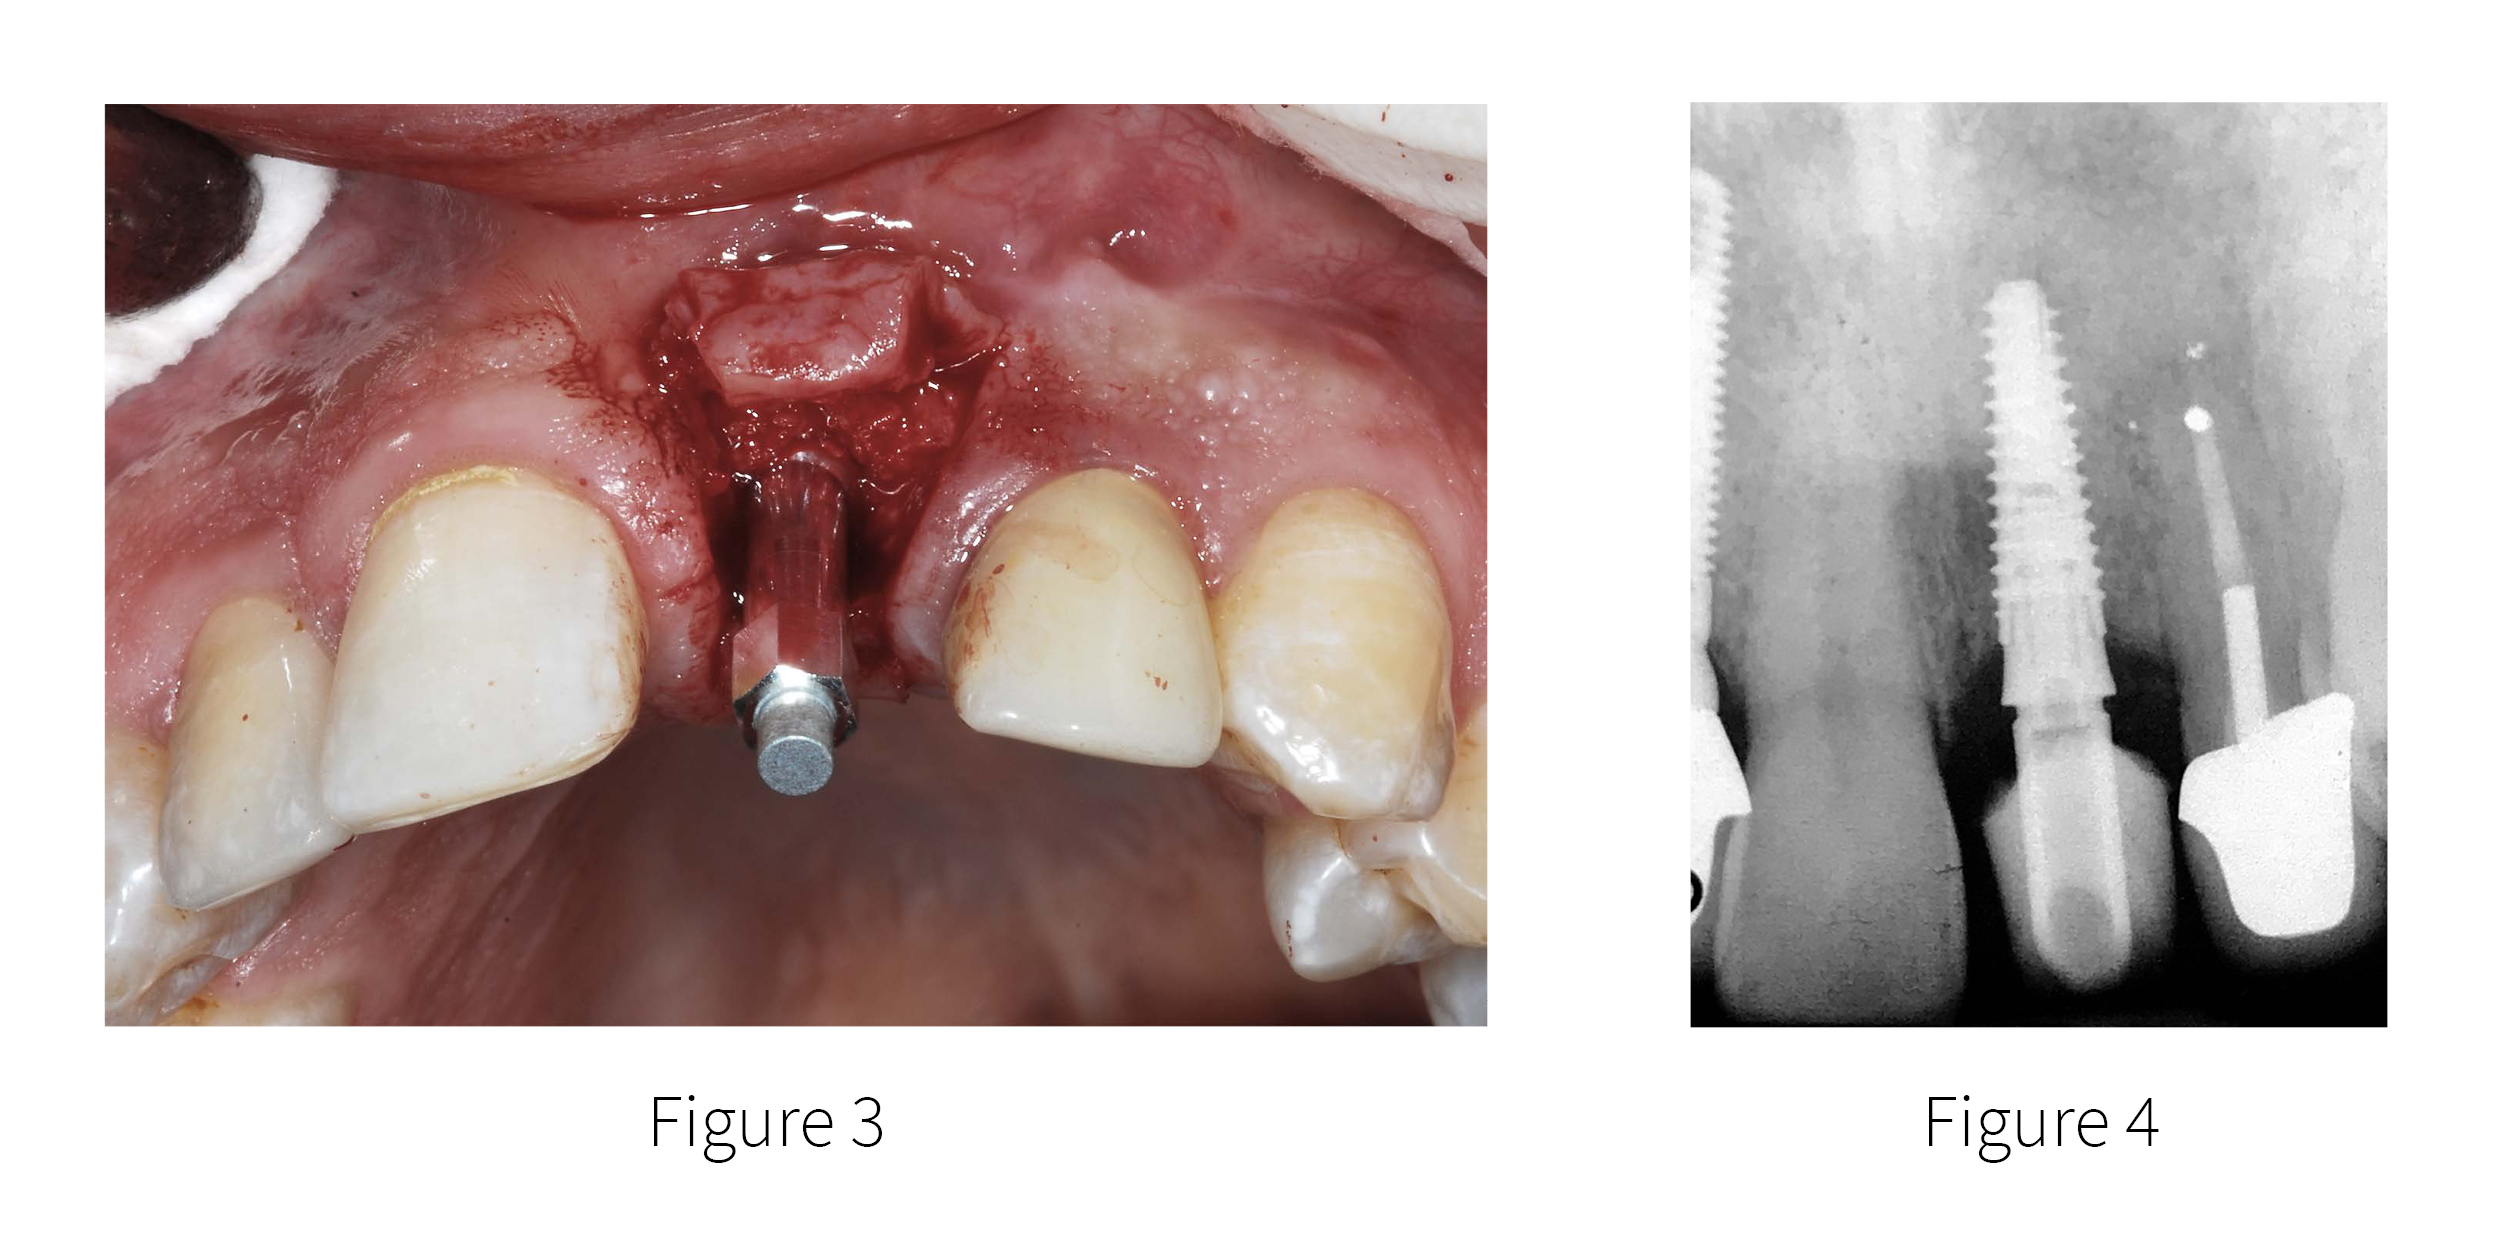

Using a papilla-sparing flap design, a soft-bone drilling protocol was utilized to engage grafted bone in the maxillary receptor site using “template-assisted” guidance (not shown). A 3.5 mm diameter by 13 mm length implant was placed (AnyRidge, Integrated Dental Systems (IDS) – MegaGen, Englewood, NJ). As this was grafted bone it was important to have an objective baseline of implant stability. The initial Osstell implant stability quotient (ISQ) was 68 [FIGURE 3]. It was elected not to immediately load the implant, and the soft tissue was approximated and sutured to achieve primary closure. The favorable design of the implant, combined with the initial Osstell ISQ value provided a high level of confidence to determine that an accelerated eight week healing period would be sufficient to achieve the integration necessary for restorative loading.

Figure 3. The SmartPeg ready for Osstell ISQ measurement after implant placement.

Figure 4. A screw-retained temporary was fabricated to aid in the maturation of the soft

Tissue sulcus.

At approximately 8 weeks the patient returned to uncover the implant. To assess the level of osseointegration, secondary Osstell ISQ values were recorded at 76 buccal, and 76 palatally, indicating improved stability. The increase in Osstell ISQ provided the confidence for restorative loading with a transitional screw-retained restoration fabricated to also assist in soft tissue maturation and emergence profile [FIGURE 4]. Therefore resonance frequency analysis (RFA) provides the practitioner with an accurate and objective measure of the osseointegration process and subsequent changes over time.